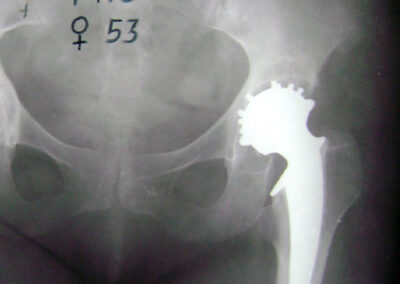

Exemplos de artroplastia cimentada e não-cimentada podem ser vistos na Fig. 2, através das radiografias. A figura ainda mostra exemplos radiográficos de artroplastias híbrida (haste femoral cimentada e componente acetabular não-cimentado) e híbrida-reversa (haste femoral não-cimentada e componente acetabular cimentado). O sucesso da artroplastia total de quadril depende basicamente de três fatores críticos: escolha do paciente, do implante e da técnica cirúrgica. Provavelmente, o determinante isolado mais importante seja a escolha apropriada do paciente. A escolha de um paciente inadequado pode comprometer o design mais avançado ou mesmo o cirurgião mais experiente (1,2,7).